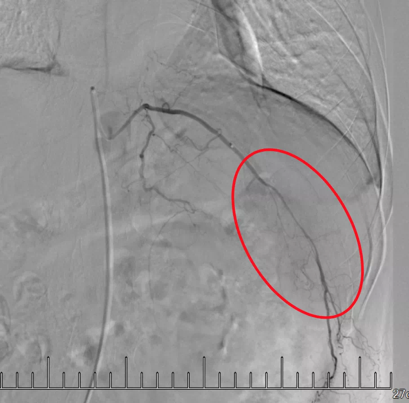

微導(dǎo)管插管到轉(zhuǎn)移瘤所在肋間動(dòng)脈

造影顯示紅圈內(nèi)“烏云”區(qū)域?yàn)槟[瘤。

灌注藥物及栓塞后“烏云”消失

肋間動(dòng)脈阻斷營(yíng)養(yǎng)來源